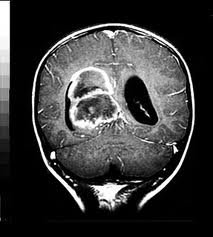

Ependimoma

Información: Un ependimoma es una neoplasia intracraneal del sistema nervioso central , que aparecen comunmente en el cuarto ventrículo en niños y en el conducto ependimario o raquídeo en la región lumbosacra en adultos. Ocasionalmente se usa el término siringomielia para los ependimomas, los cuales pueden aparecer en la neurofibromatosis tipo II. Los ependimomas se tratan quirúrgicamente, los cuales, con una resección total, se asocian a pronósticos excelentes de sobrevivencia. A los 5 años se espera una sobrevida de 80%, aunque no todos los ependimomas puede resecarse completamente, por lo que se emplea además la radioterapia y quimioterapia.1

Los ependimomas constituyen cerca del 5% de los gliomas intracraneales de los adultos y un 10% de los tumores del sistema nervioso central en niños. Su aparición ocurre como promedio a los 5 años y luego a los 35 años de edad. En la infancia aparecen en los ventrículos especialmente el cuarto ventrículo y en los adultos aparecen en el canal que contiene a la médula espinal.1

Cuando se instalan en el cerebro, pueden producir dolor de cabeza, náuseas y vómitos al obstruir el flujo del líquido cefalorraquídeo. La obstrucción puede también causar hidrocefalia. Otros síntomas incluyen la pérdida del apetito, dificultad para dormir, pérdida temporal de distinguir colores, y de la memoria, entre otros.